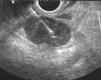

En primer lugar se efectuó una ecoendoscopia diagnóstica usando un ecoendoscopio radial con frecuencias de 5 y 20 MHz (GF UM20 y GF UM160, Olympus America Inc., Melville, NY, EE UU). En todos los casos se realizó una exploración sistemática del mediastino posterior y medio, y de los territorios ganglionares accesibles a la USE (regiones 4R, 4L, 5, 7, 8 y 9) con el fin de identificar y caracterizar morfológicamente las lesiones y establecer la relación entre éstas y las estructuras vecinas (figs. 1 y 2).

Fig. 1. Masa paraesofágica izquierda de características malignas: heterogénea y mal delimitada. Se trataba de un liposarcoma.